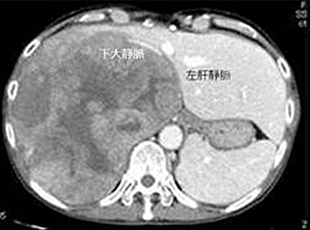

2. Ante-situm法による肝切除

肝静脈根部に腫瘍が存在して通常の肝切除では切除不可能な症例に対して生体肝移植の技術を応用した体内冷却肝灌流法を用いたAnte-situm法による肝切除を行っています。下大静脈が腫瘍の浸潤を受けている場合には人工血管による置換を行います。これまでの実績は8例(京都大学で5例、秋田大学で3例)です。この手術の概要は2005年8月10日に秋田さきがけ新報の「医療新世紀・進むがん治療・秋田大学医学部の取り組み」に紹介されました。(手技は確立されておりますが、試験的手術法の段階であり、一般的治療法では助けられない患者さんに限って考慮しております。)